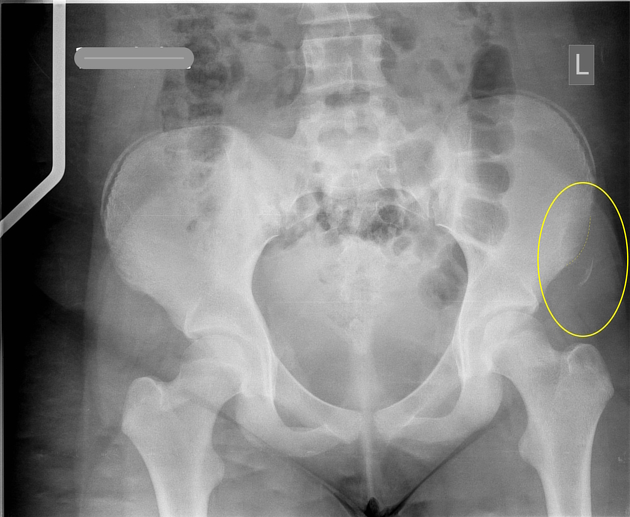

What could have caused this fracture?

ASIS avulsion fracture caused by the sartorius muscle from forceful flexion, lateral rotation or abduction of the hip